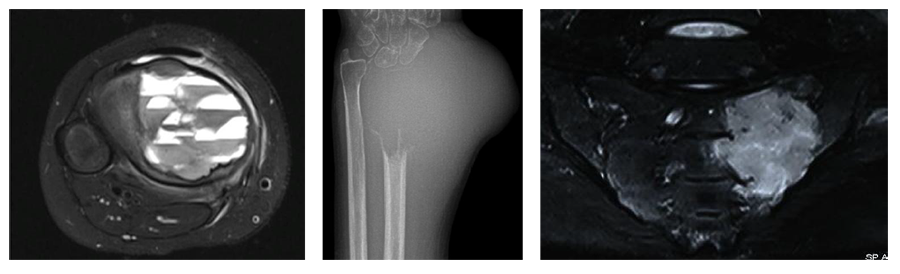

Опухоли костей являются редкими поражениями. Большая часть таких опухолей - доброкачественные образования, которые часто обнаруживаются случайно при радиологических исследованиях, проводимых по другим причинам. Что касается жалоб, они обычно проявляются отеком и болью. В редких случаях они обнаруживаются вследствие вызванного ими перелома в месте их расположения. Наиболее часто встречающимися доброкачественными образованиями являются остеоид-остеома, остеохондрома (экзостоз), энхондрома, неоссифицирующая фиброма, эозинофильная гранулема, простая костная киста, фиброзная дисплазия и внутрикостная липома / ганглия.